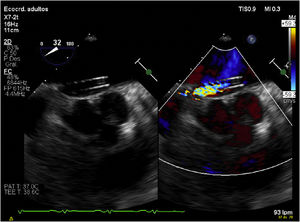

La intervención se realizó de manera programada en quirófano bajo control radiológico y ecocardiográfico (figs. 2 y 3).